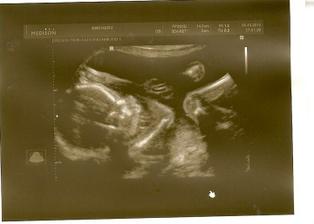

Pořídíme Míše Ríšu 🙂

tak se nám zadařilo počít sourozence, opět to byl fofr, první měsíc, takže opět trochu šok i když příjemný

zatím všechno vypadá krásně, mamince je dobře, doktoři jí hlídají na všech frontách, tak snad se nám tentokrát podaří dočkat se termínu 22.2.2011 🙂